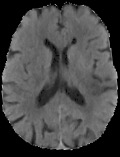

Accurate infarct segmentation in non-contrast CT (NCCT) images is a crucial step toward computer-aided acute ischemic stroke (AIS) assessment. In clinical practice, bilateral symmetric comparison of brain hemispheres is usually used to locate pathological abnormalities. Recent research has explored asymmetries to assist with AIS segmentation. However, most previous symmetry-based work mixed different types of asymmetries when evaluating their contribution to AIS. In this paper, we propose a novel Asymmetry Disentanglement Network (ADN) to automatically separate pathological asymmetries and intrinsic anatomical asymmetries in NCCTs for more effective and interpretable AIS segmentation. ADN first performs asymmetry disentanglement based on input NCCTs, which produces different types of 3D asymmetry maps. Then a synthetic, intrinsic-asymmetry-compensated and pathology-asymmetry-salient NCCT volume is generated and later used as input to a segmentation network. The training of ADN incorporates domain knowledge and adopts a tissue-type aware regularization loss function to encourage clinically-meaningful pathological asymmetry extraction. Coupled with an unsupervised 3D transformation network, ADN achieves state-of-the-art AIS segmentation performance on a public NCCT dataset. In addition to the superior performance, we believe the learned clinically-interpretable asymmetry maps can also provide insights towards a better understanding of AIS assessment. Our code is available at https://github.com/nihaomiao/MICCAI22_ADN.